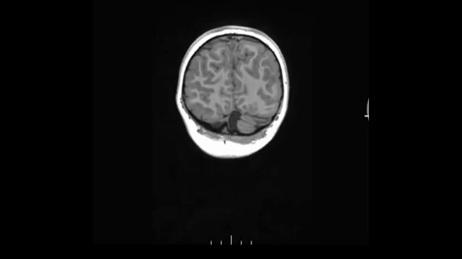

接下来,还能搞什么序列。 首先是癫痫经典序列容积CUBE T2FLAIR成像。

接着,容积解剖成像序列T1W MP – RAGE。等体素扫描,三方面重建轴、矢和冠状面自动重建。

并未见到显著异常。 癫痫三大利器:容积T2 FLAIR、容积T1以及高分辨COR T2W。